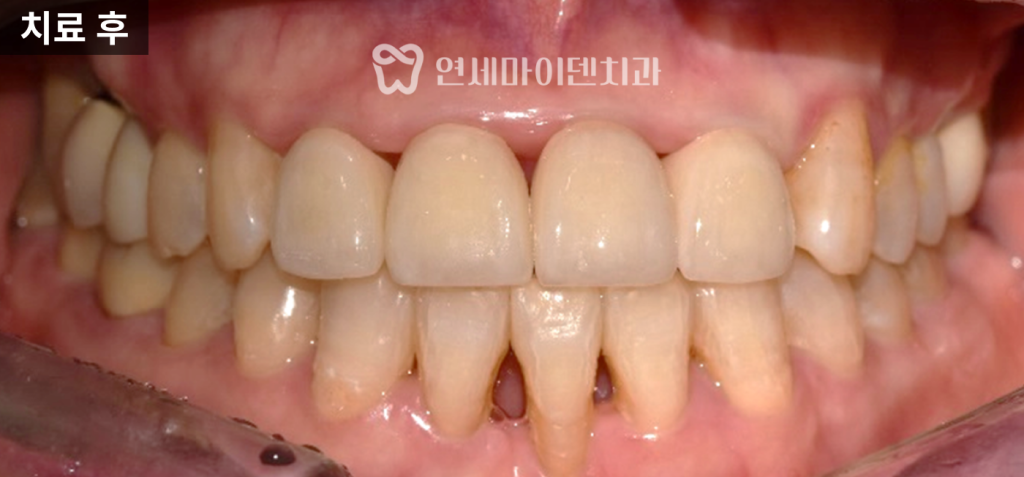

치료 결과와 변화

교정 마무리 후 상악 앞니는 새로운 보철물로 교체했고,

아래 앞니는 배열이 개선된 상태에서

교정장치를 제거했습니다.

방사선 사진 비교에서도

추가적인 잇몸뼈 손실은 관찰되지 않았으며,

일부 부위에서는 오히려 안정화된 모습이 확인되었습니다.

옆모습에서도 아래 앞니가 다소 뒤로 이동하고,

위앞니 보철의 심미성이 개선된 것을 확인할 수 있었습니다.